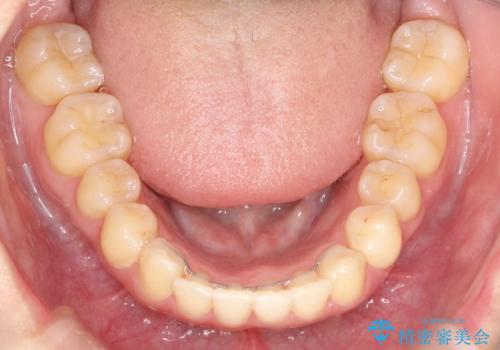

- 前歯が少し前に出ているのが気になるとのことで来院されました。

インビザラインにて上顎の歯を全体的に後方に移動させて前歯を引っ込める計画としました。